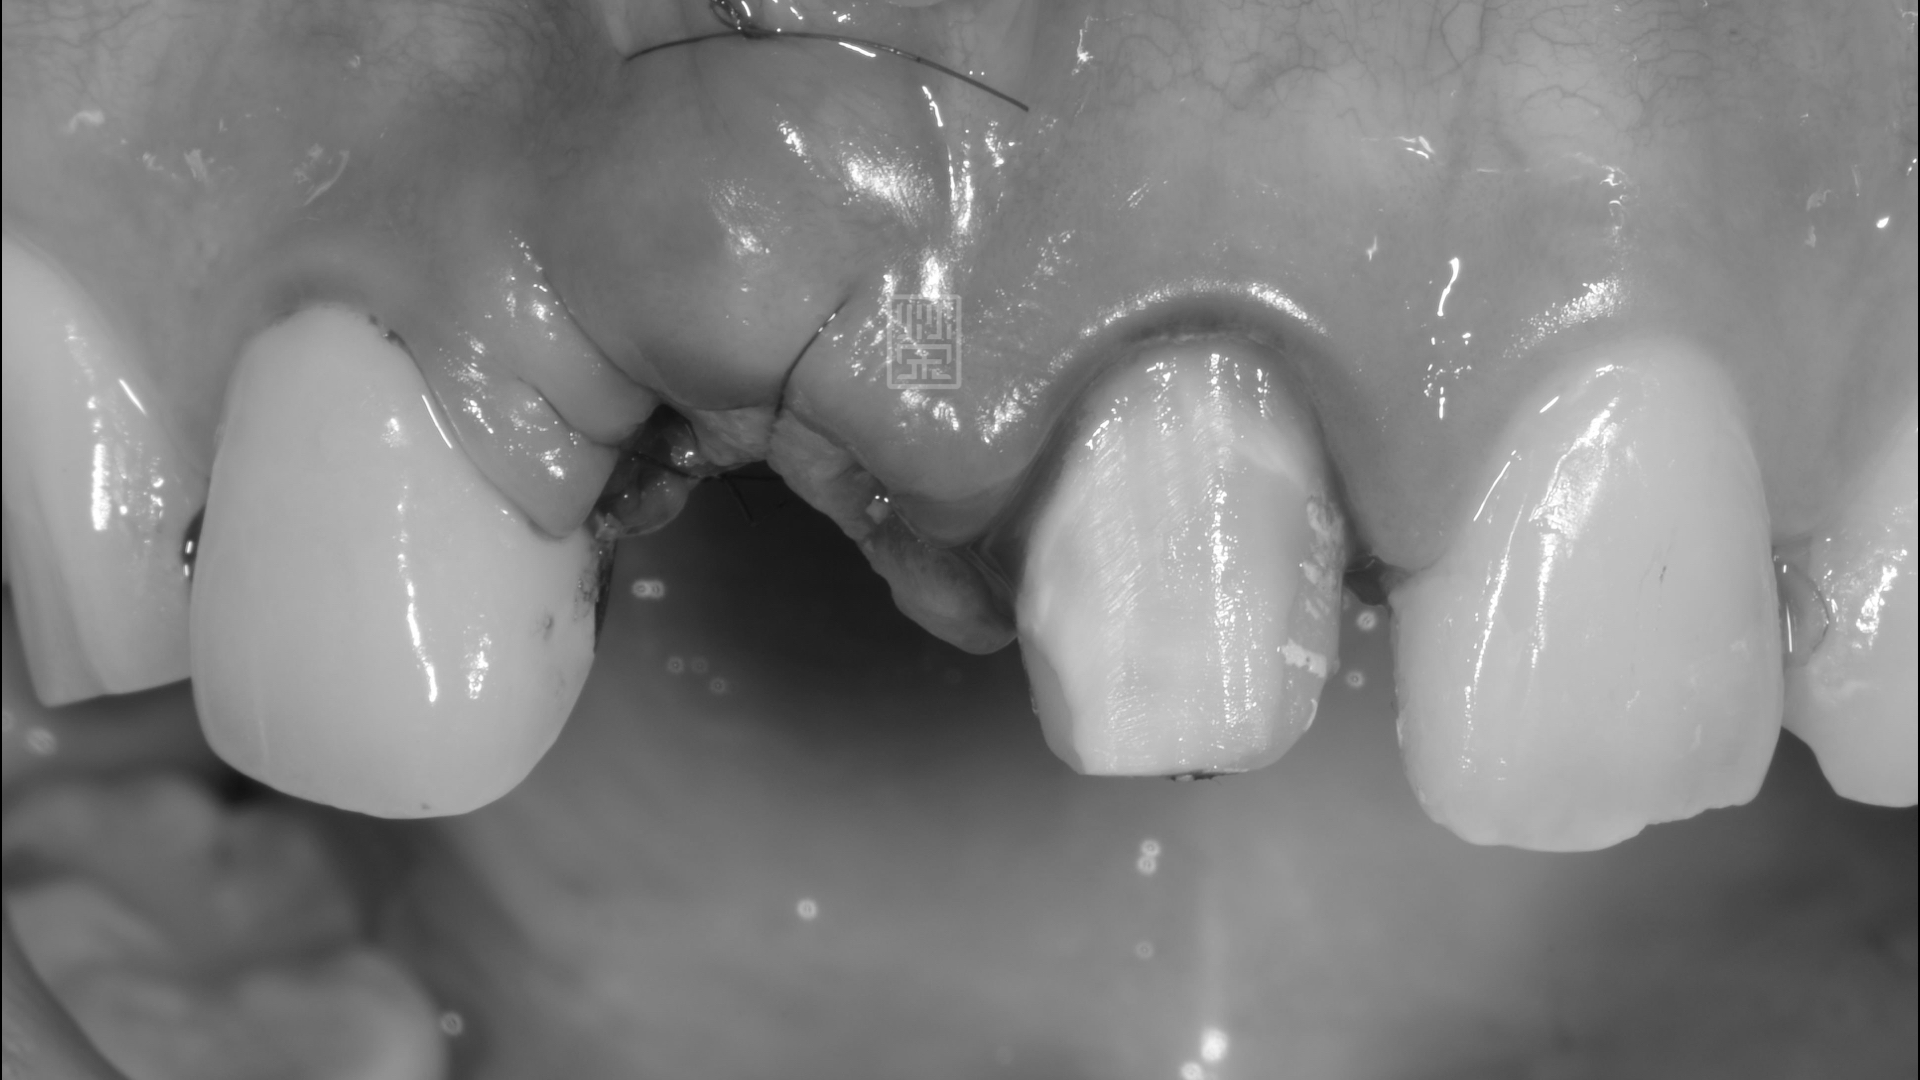

植牙手術合併牙齦轉移